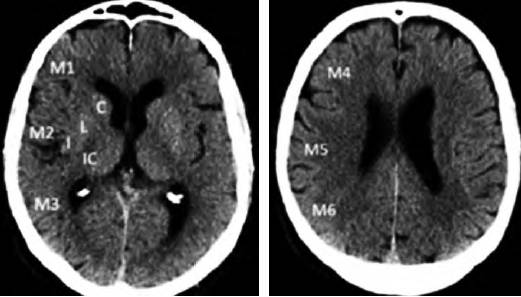

3.2.1 ASPECTS评分

ASPECTS评分是基于NCCT评估MCA区域早期缺血改变简单而系统的一种方法。将MCA供血区各主要功能区分别赋分(4个皮层下区:尾状核C、豆状核L、内囊IC、岛叶I;6个皮层区,标志为M1-M6)(图1),共计10 分,每累及一个区域减去1分,即正常脑CT为10分,MCA供血区广泛梗死则为0分。

图1 ASPECTS评分中大脑中动脉供血区功能分区注:皮层下区:C:尾状核(caudate);L:豆状核(lentiform);IC:内囊(internal capsule);I:岛叶(insular ribbon);皮层区:M1-M6。ASPECTS:Alberta卒中项目早期计算机断层扫描评分